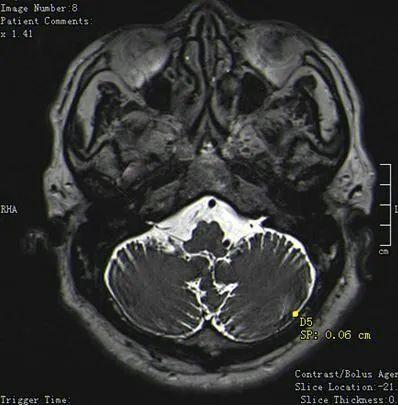

第三例舌咽神经痛王某,女,52岁,“右侧阵发性咽后壁疼痛一月余”入院

舌咽神经痛与右侧小脑后下分支血管关系紧密

术中暴露神经与血管

游离舌咽神经与迷走神经

电凝舌咽神经支

剪断杜绝后患

术后患者疼痛症状明显缓解,无声音嘶哑,吞咽呛咳等并发症!